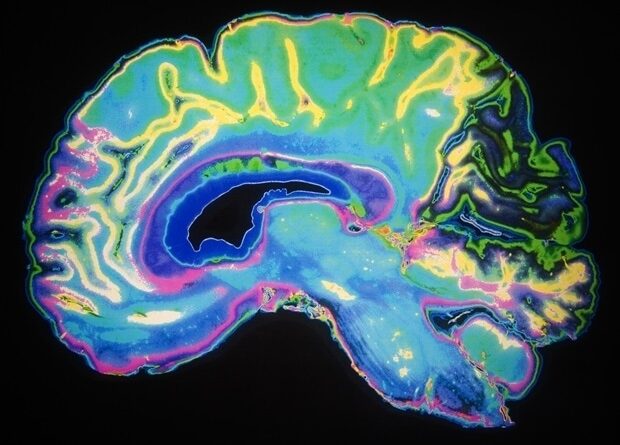

For this study, researchers used susceptibility-weighted imaging to analyze the effects that COVID-19 has on the brain. Magnetic susceptibility denotes how much certain materials, such as blood, iron and calcium, will become magnetized in an applied magnetic field. This ability aids in the detection and monitoring of a host of neurologic conditions including microbleeds, vascular malformations, brain tumors and stroke.

The researchers analyzed the susceptibility-weighted imaging data of 46 COVID-recovered patients and 30 healthy controls. Imaging was done within six months of recovery. Among patients with long COVID, the most commonly reported symptoms were fatigue, trouble sleeping, lack of attention and memory issues.

MRI results showed that patients who recovered from COVID-19 had significantly higher susceptibility values in the frontal lobe and brain stem compared to healthy controls. The clusters obtained in the frontal lobe primarily show differences in the white matter.

Portions of the left orbital-inferior frontal gyrus (a key region for language comprehension and production) and right orbital-inferior frontal gyrus (associated with various cognitive functions including attention, motor inhibition and imagery, as well as social cognitive processes) and the adjacent white matter areas made up the frontal lobe clusters.

The researchers also found a significant difference in the right ventral diencephalon region of the brain stem. This region is associated with many crucial bodily functions, including coordinating with the endocrine system to release hormones, relaying sensory and motor signals to the cerebral cortex and regulating circadian rhythms (the sleep-wake cycle).